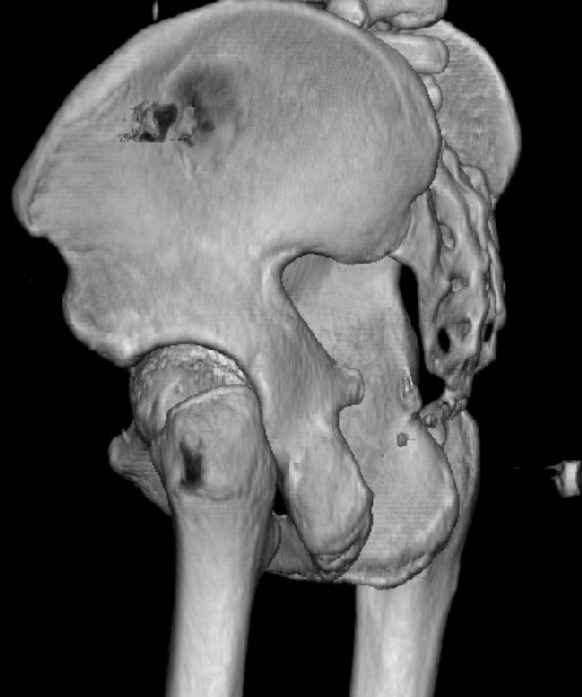

The last two images from the 3-D CT scan certainly makes the fracture look worse than the plan radiographs.

Some more images. Does it help to guess which part of the acetabulum is displaced?

Normal appearing SI joints and a healed posterior column limb... my bet's on caudal segment displacement.